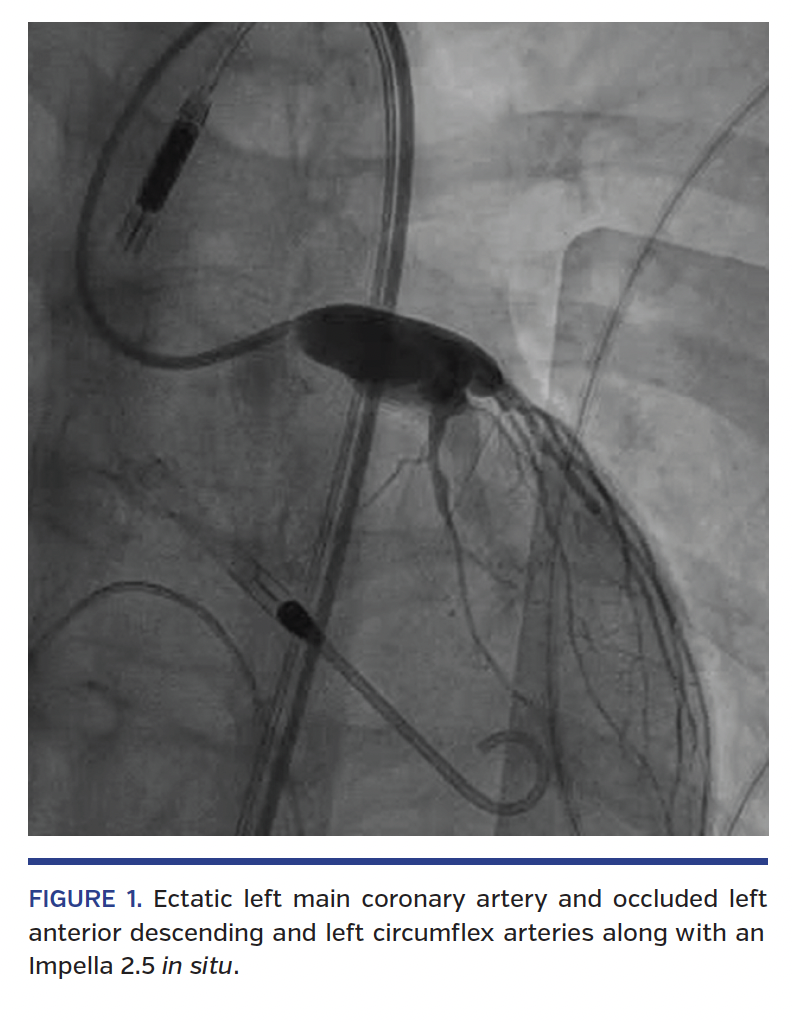

A 15-year-old male with past medical history of Kawasaki disease presented to our emergency room with complaints of severe retrosternal, crushing chest pain at rest associated with nausea and diaphoresis. Physical examination revealed dry mucous membranes. Electrocardiogram showed acute ST-elevation myocardial infarction and laboratory testing showed elevated cardiac enzymes. He was taken to cardiac catheterization laboratory emergently with placement of Impella 2.5 (in view of decreasing left ventricular function) followed by coronary angiography, which showed significantly ectatic left main coronary artery, left anterior descending (LAD) coronary artery, left circumflex (LCX) coronary artery, and right coronary artery (RCA), with associated thrombotic occlusion of the LAD, LCX, and RCA (Figure 1). Intracoronary thrombolysis of the infarct-related artery (RCA) was performed using tissue plasminogen activator 250,000 U/kg 3 times daily for 2 days (Figure 2). Multiple rounds of aspiration thrombectomy followed by balloon angioplasty of the LAD failed to completely restore the flow into the distal LAD secondary to re-occlusion from thrombus formation (Figures 3-5). The patient recovered well with improvement in myocardial pump function, with an ejection fraction of approximately 45%-50% on discharge.